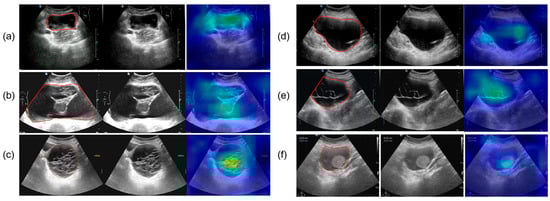

All ultrasound images were obtained from the Picture Archiving and Communication Systems (PACS). Images were acquired using abdominal probes with a frequency range of 1–6 MHz and transvaginal probes with a frequency range of 2–9 MHz. For each patient, the images representing the largest lesion diameter and most complex morphology were selected. Figure 2 provides representative examples of selected cases from this study. Senior radiologists precisely annotated tumor location and boundaries using the Labelme tool (Version 4.5.9, Cambridge, MA, USA) [18]. The lesion regions were then manually cropped and saved as separate images, which were converted to grayscale to standardize the input format for model training.

Figure 2.

The parts circled in red in the image represent the lesions we labelled. (a) A 42-year-old patient with a serous cystadenoma. (b) A 35-year-old patient with a mature cystic teratoma. (c) A 48-year-old patient with a borderline mucinous tumor. (d) A 52-year-old patient with high-grade serous adenocarcinoma. (e) A 65-year-old patient diagnosed with an ovarian fibroma; (f) A 48-year-old patient with an adult-type granulosa cell tumor.